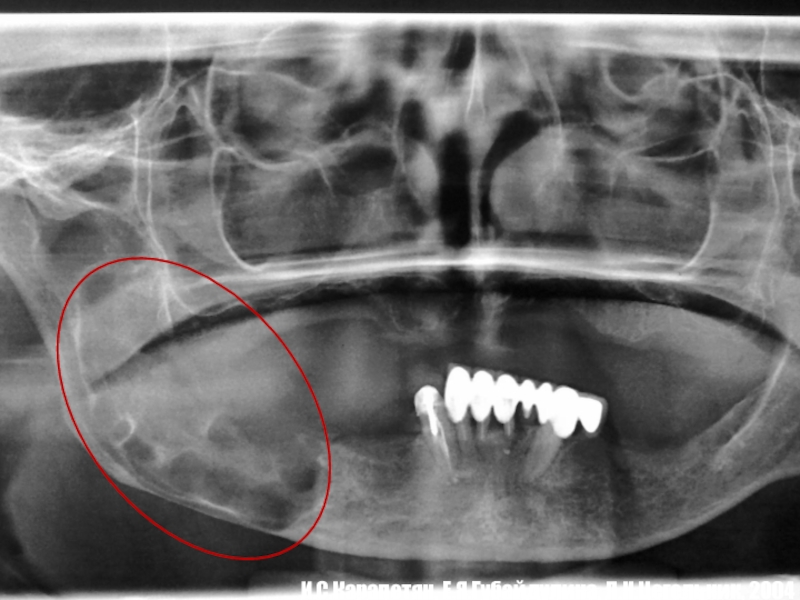

Рентгеновские снимки посттравматического остеомиелита челюсти: Медицинские случаи

Раздел: Образы вокруг